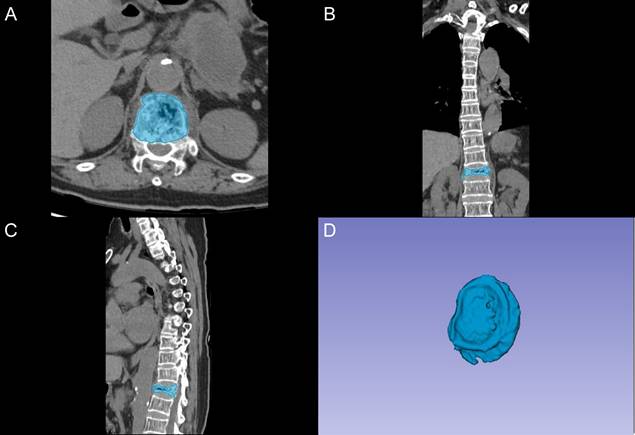

The segmentation of vertebral bodies was conducted using 3D Slicer software (version 5.0.2) by two fellowship-trained radiologists with 8 and 10 years of experience in spinal imaging, who were blinded to clinical outcomes. A standardized segmentation protocol was implemented, as demonstrated in Figure 1. The process began with semi-automatic delineation of vertebral margins utilizing density-based thresholding to distinguish bone from adjacent soft tissues. Manual adjustments were subsequently performed to optimize boundary definition, particularly at regions of complex anatomical interfaces. The final region of interest (ROI) encompassed the complete vertebral body, including both the cancellous core and cortical shell.

Figure 1

Vertebral segmentation protocol and three-dimensional reconstruction. A: Axial CT image showing semi-automatic segmentation of the vertebral body (blue). B: Coronal reconstruction demonstrating the segmented vertebral region. C: Sagittal view of the segmented vertebral body. D: Three-dimensional reconstruction of the segmented vertebral volume of interest.